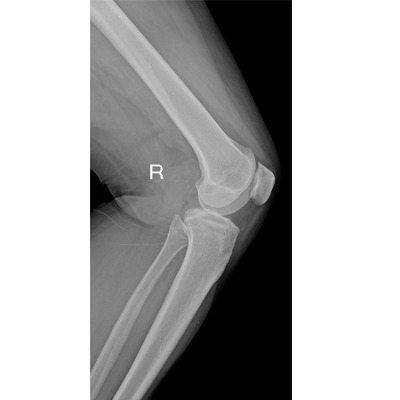

輕量化設(shè)計(jì) 小巧靈活 PLX5100

用于影像科、急診室、病房、ICU、手術(shù)室等多場(chǎng)景應(yīng)用。

● 數(shù)字化無線平板成像,操作簡(jiǎn)便,成像質(zhì)量高